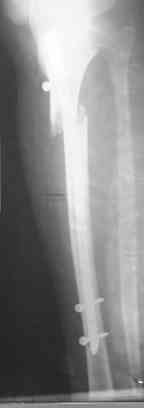

Re: Интрамедуллярный остеосинтез. Как избежать смещение?

Савранский Александр 30 Декабрь 2006, 02:06

Оставить как есть,но с нагрузками не торопиться,на будущее-нет ЭОП,есть рентген-интраоперационный.

да какие последствия, разве боль, косметический дефект, на гвозде и так срастетсЯ, а какие требования? если высокие- коррекция оси в АВФ, после удаления гвоздя, затем ORIF доступными имплантами (если нет ЭОПа).С Н.Г.

не трогайте ничего ! срастется . Единственно стоит проверить соответствие осей г\ст и к\с (чтобы не было ротации !!!)

конечно в данном случае все хорошо срастется.На будущее при таких высоких переломах,хорошо помогают направляющие винты.Они вводятся спереди назад(до введения стержня) для предотвращения бокового смещения или снуружи ввнутрь ,для предотвращения передне - заднего.Они не дают стержню сместить перелом.ЭОП не нужен,обычный рентген о опер.достаточен.

Удобнее для этих целей использовать спицы. Их и быстрее/легче ввести, и в случае слишком агрессивного введения они гнутся и удается провести гвоздь, в то время как с винтом он заклинится или расколется кость.